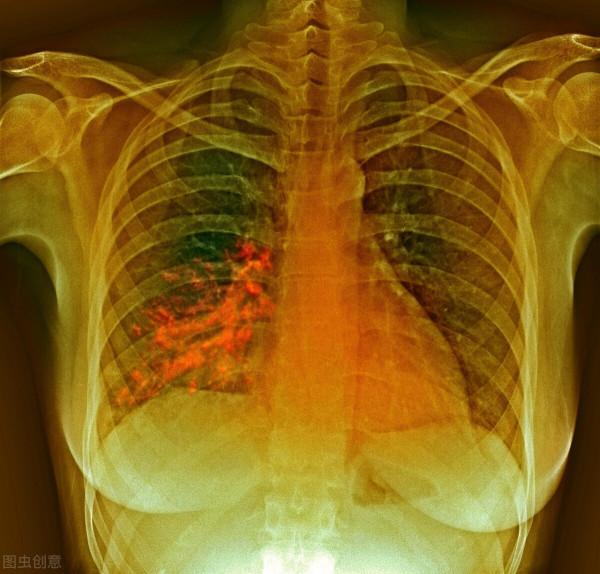

嗆咳會導致食物進入氣道,沿氣道進入肺臟,這些食物殘渣對於無菌環境的肺而言,屬於感染源,會導致肺部感染,引起吸入性肺炎,出現發熱、咳嗽、咳痰、喘憋、氣短,嚴重的危及生命。鼻飼飲食,可避免嗆咳發生,減少肺炎機率。